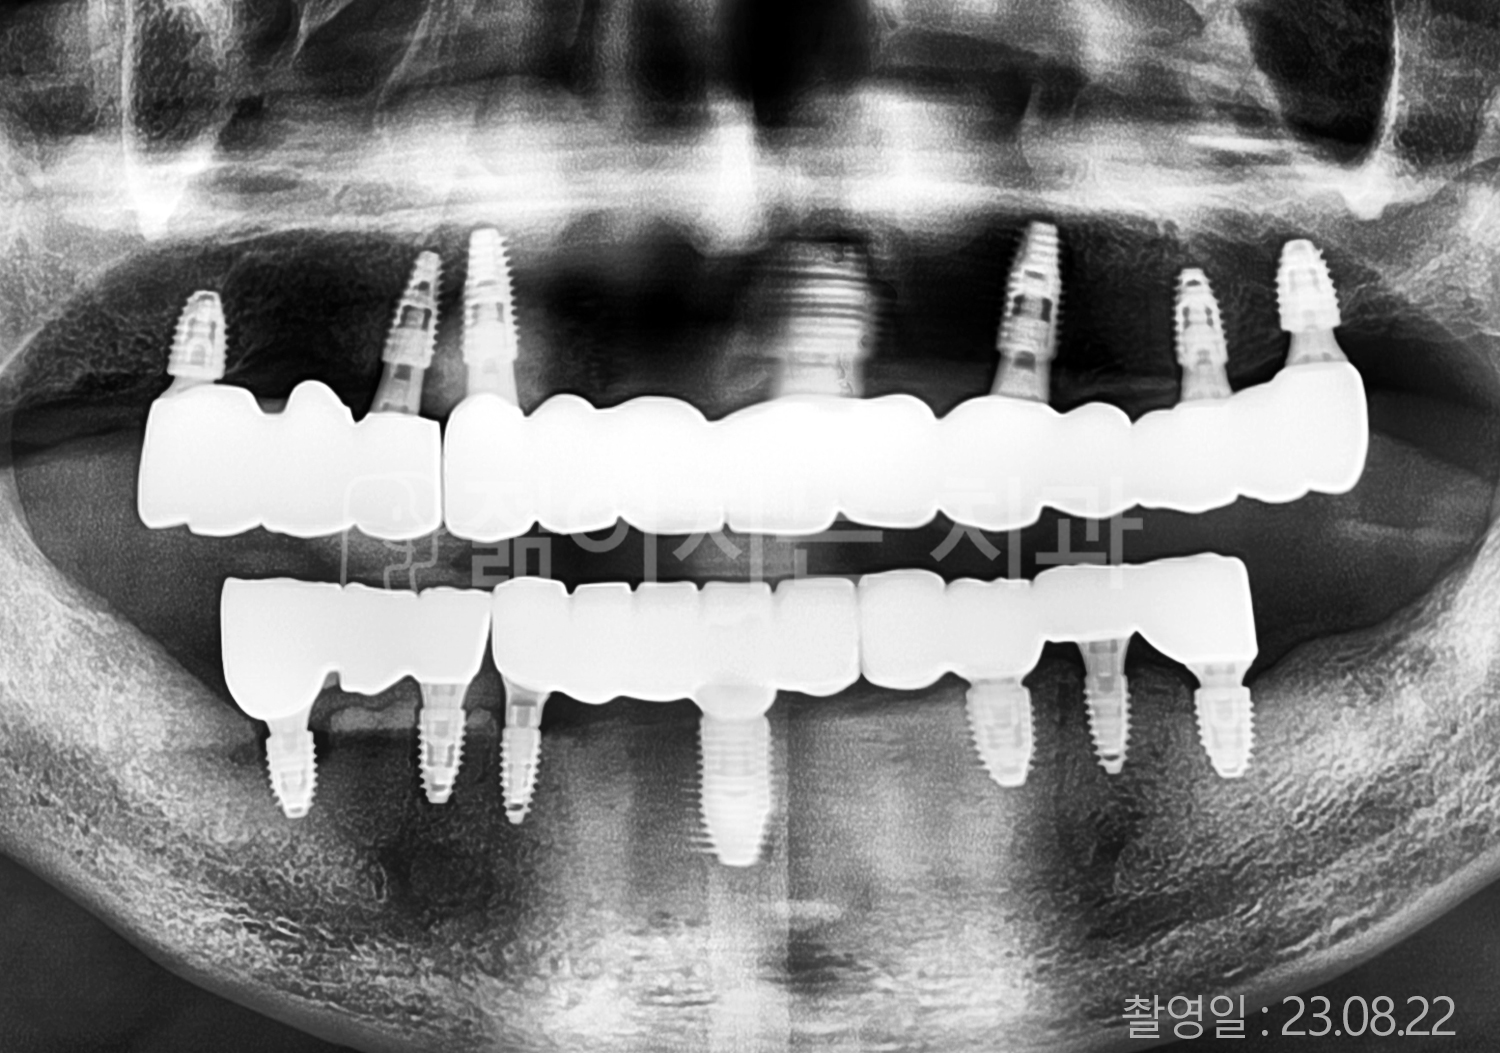

• 50대 고혈압, 고지혈증 전체치아 10개 이상 임플란트